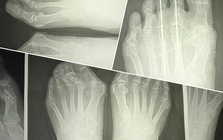

靴の害、外反母趾

靴の健康被害、外反母趾。

外反母趾の問題は痛みだけではありません。

その変形症状から多くの身体の不具合と

Hallux valgus